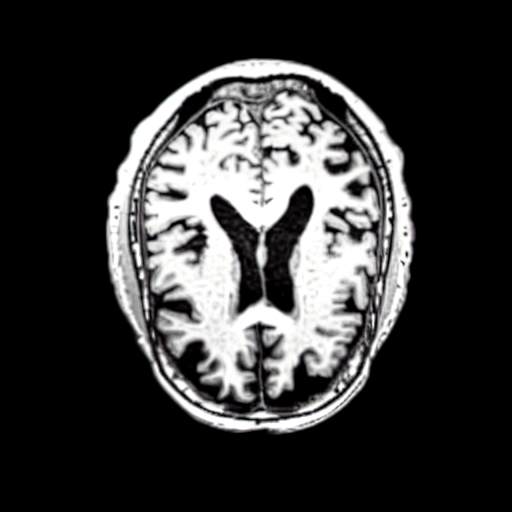

We use the Pix2Pix Zero model with a basic fine-tuned Stable Diffusion model to generate healthy brain MRIs from ones diagnosed with Alzheimer’s Disease and vice versa. We generate the counterfactual images by negating the ground truth label of the 200 test samples and conditioning the model on the negated label value and the source image. We compute image quality metrics, as well as the AUC, using a disease classification model trained on 600 real brain MRI slices (300 AD, 300 CN). Additionally, we determine the Structure Similarity Inced (SSIM) between the target and the source image to determine how well the identity of the source image is retained. The qualitative results in Fig. 6 , illustrate four examples from our two editing directions: from AD to CN and from CN to AD, respectively. When transitioning from AD to CN, the model primarily reduces the size of the ventricles. Conversely, in the CN to AD transformation, the ventricle size increases, accompanied by a worsening of brain atrophy.